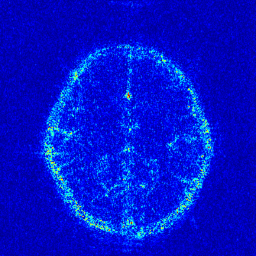

We take the difference between the absolute reconstruction error of zero-filled and the compared CS-MRI methods and only keep the nonnegative values, which can be formulated as

md=(|xfsx¯p||xfs𝒵(y)|)+.subscript𝑚𝑑subscriptsubscript𝑥𝑓𝑠subscript¯𝑥𝑝subscript𝑥𝑓𝑠𝒵𝑦m_{d}={\left({\left|{{x_{fs}}-{\overline{x}_{p}}}\right|-\left|{{x_{fs}}-{\cal Z}(y)}\right|}\right)_{+}}. (8)

Where the operator ()+subscript{\left(\cdot\right)_{+}} set the negative values to zero. We only keep the nonnegative values in the map, which results the filtered difference map. We show the corresponding filtered difference map mdsubscript𝑚𝑑m_{d} in figure 3 in the range [0 0.2]. The bright region means the better accuracy of zero-filled reconstruction. We observe the zero-filling reconstruction provide better reconstruction accuracy on some regions, indicating the information loss in the reconstruction occurs.

Figure 3: The filtered difference map d𝑑d between the reconstruction errors of the zero-filled reconstruction and recent CS-MRI inversions.